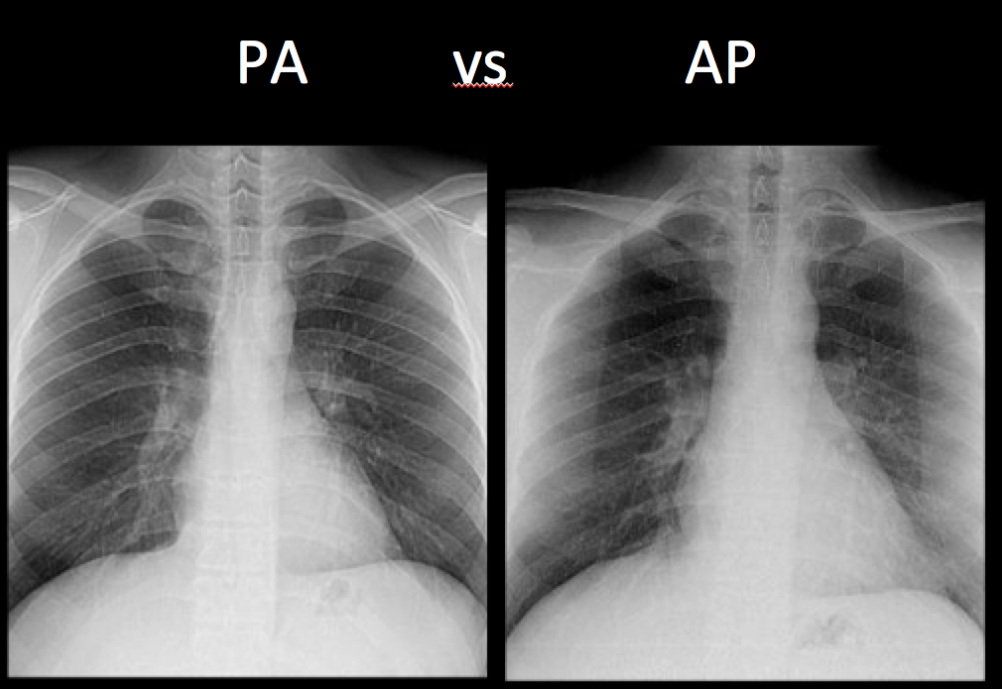

Posteroanterior View (PA)

A standard view for chest X-rays taken with the X-ray beam directed from posterior to anterior.

Anteroposterior View (AP)

A chest X-ray view taken with the X-ray beam directed from anterior to posterior.